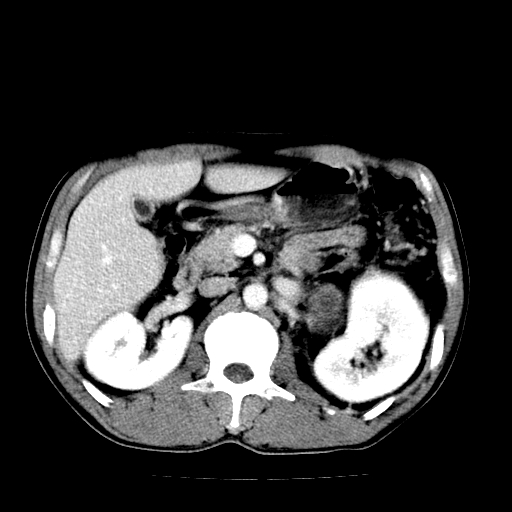

以下是引用天南地北在2007-4-30 13:36:00的发言:[br]支持慢性胰腺炎伴有假性囊肿

以下是引用andymaomao在2007-4-30 14:28:00的发言:[br]支持:1.慢性胰腺炎并假性囊肿形成可能;[br] 2.左肾形态稍增大,旋转不良。